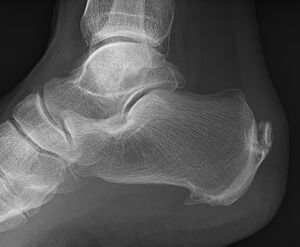

| صورة بالأشعة توضح نبتة عظمية على الجوانب الخلفية والسفلية من العقب | |

مهماز العقب (إنگليزية: calcaneal spur، يُعرف أيضاً باسم مهماز الكعب إنگليزية: heel spur)، هو نتوء عظمي ينمو من عظام الكعب.[1] عادة ما يكتشف مهماز العقب بالأشعة السينية.[2] وهو يشكل العرن.

المهماز العقبي الخلفي يقع على الجانب الخلفي للعقب وهو استجابة طبيعية لالتهاب اللفافة الأخمصية على مدار الوقت، لكنه يرتبط أيضاً بالتهاب الفقار المقسط (عادة لدى الأطفال). يتطور المهماز العقبي الخلفي على ظهر الكعب عند مدخل وتر أخيل.[3]

المهماز العقبي السفلي هو تكلس في العقب، الذي يقع أعلى اللفافة الأخمصية عند مدخل اللفافة الأخمصية. غالباً ما يكون المهماز العقبي الخلفي كبياً وملموساً من خلال الجلد وقد يحتاج إلى إزالته كجزء من علاج التهاب وتر أخيل.[3]

يمكن الكشف عن مهماز العقب بالفحص البدني متبعاً بإجراء الأشعة السينية جانبية للقدم.[citation needed]